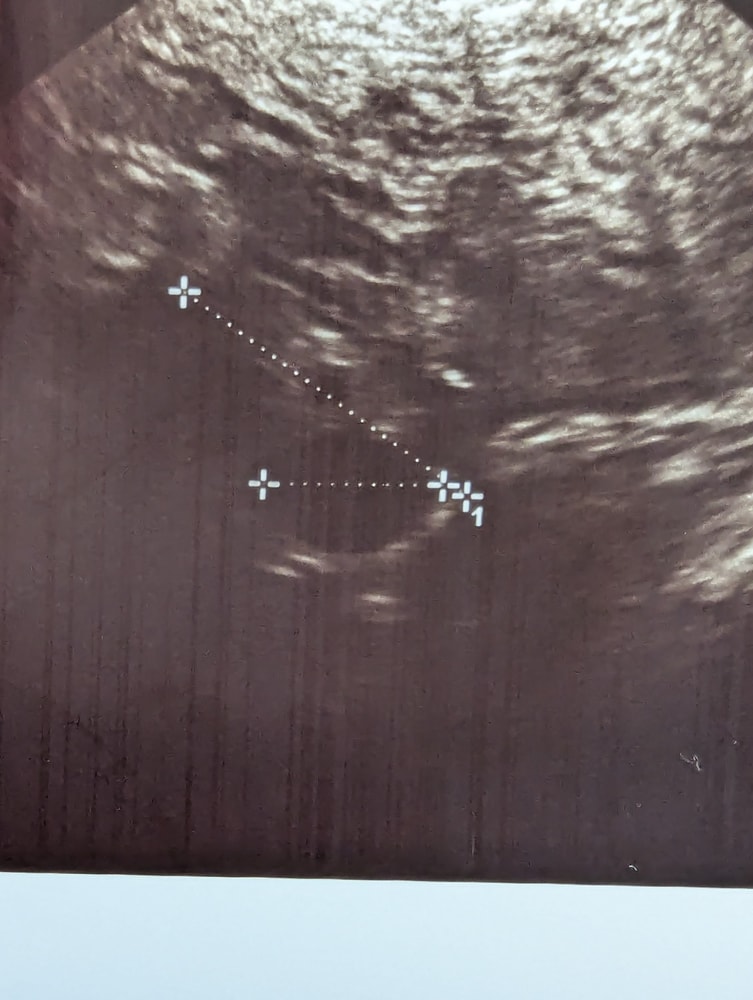

Фолликулы, да, не ЖТ? Неужели ановуляторный цикл будет...😞

Это сегодня УЗИ⬆️⬆️⬆️

Неделю назад было так ⬇️⬇️⬇️ нижний фолликул был 14 мм, сегодня15мм...

Наталья, верхний 17 мм, нижний 15мм, а неделю назад нижний был 14 мм, не вырос вообще...